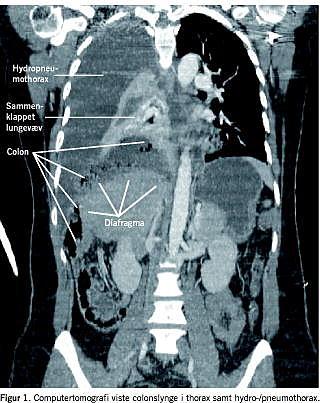

Den efterfølgende morgen blev der foretaget ekkokardiografi, som var normal. Computertomografi afslørede højresidig hydro-/pneumothorax (Figur 1 ). Endvidere sås en 11 × 7,5 × 6 cm stor kavitet med væskespejl, som strakte sig paramediastinalt og ned til diafragma. Den tentative diagnose var lungeabsces. Der anlagdes pleuradræn, hvori der udtømtes 1.000 ml tyndtflydende, rødbrun og ildelugtende væske. Patienten overflyttedes til Thoraxkirurgisk Afdeling.

På Thoraxkirurgisk Afdeling blev der foretaget åben torakotomi. Her fandt man en perforeret caecum/colon ascendens, som hernierede op gennem en defekt på ca. 2 × 2 cm lateralt i den højre diafragmakuppel (centrum tendineum). Herniet reponeredes intraabdominalt, der foretoges ileo-caecal resektion med terminal ileostomi. Den endelige diagnose var således kongenit diafragmahernie med inkarceret colonindhold.